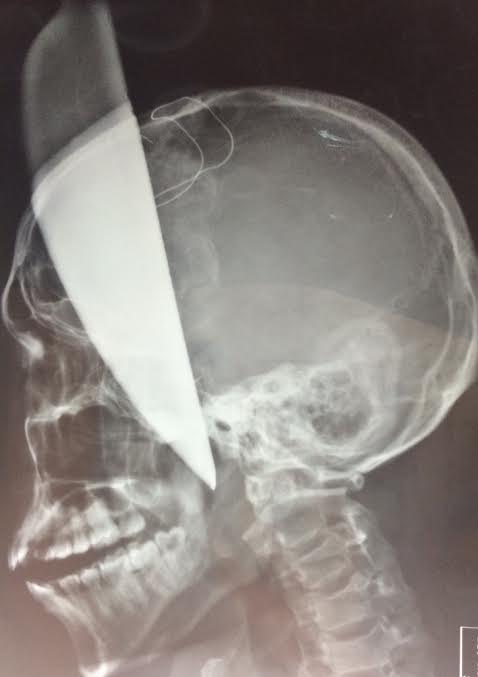

Một nam thanh niên 25 tuổi đã được chuyển đến bệnh viện Việt Đức trong tình trạng bị dao bầu dài 40cm đâm xuyên thái dương trái qua hộp sọ.

Thông tin trên báo Dân Trí cho biết, sáng ngày 18/8, một nam thanh niên nhập viện trong tình trạng nguy kịch khi bị dao bầu dài gần 40cm bị cắm xuyên qua não.

Hình ảnh dao bầu xuyên qua não nạn nhân. Ảnh: Tuổi Trẻ |

Do dao cắm sâu vào xương sọ, các bác sĩ đã phải dùng máy mài xương để lấy dao ra, tránh làm tổn thương và tránh đứt mạch máu.